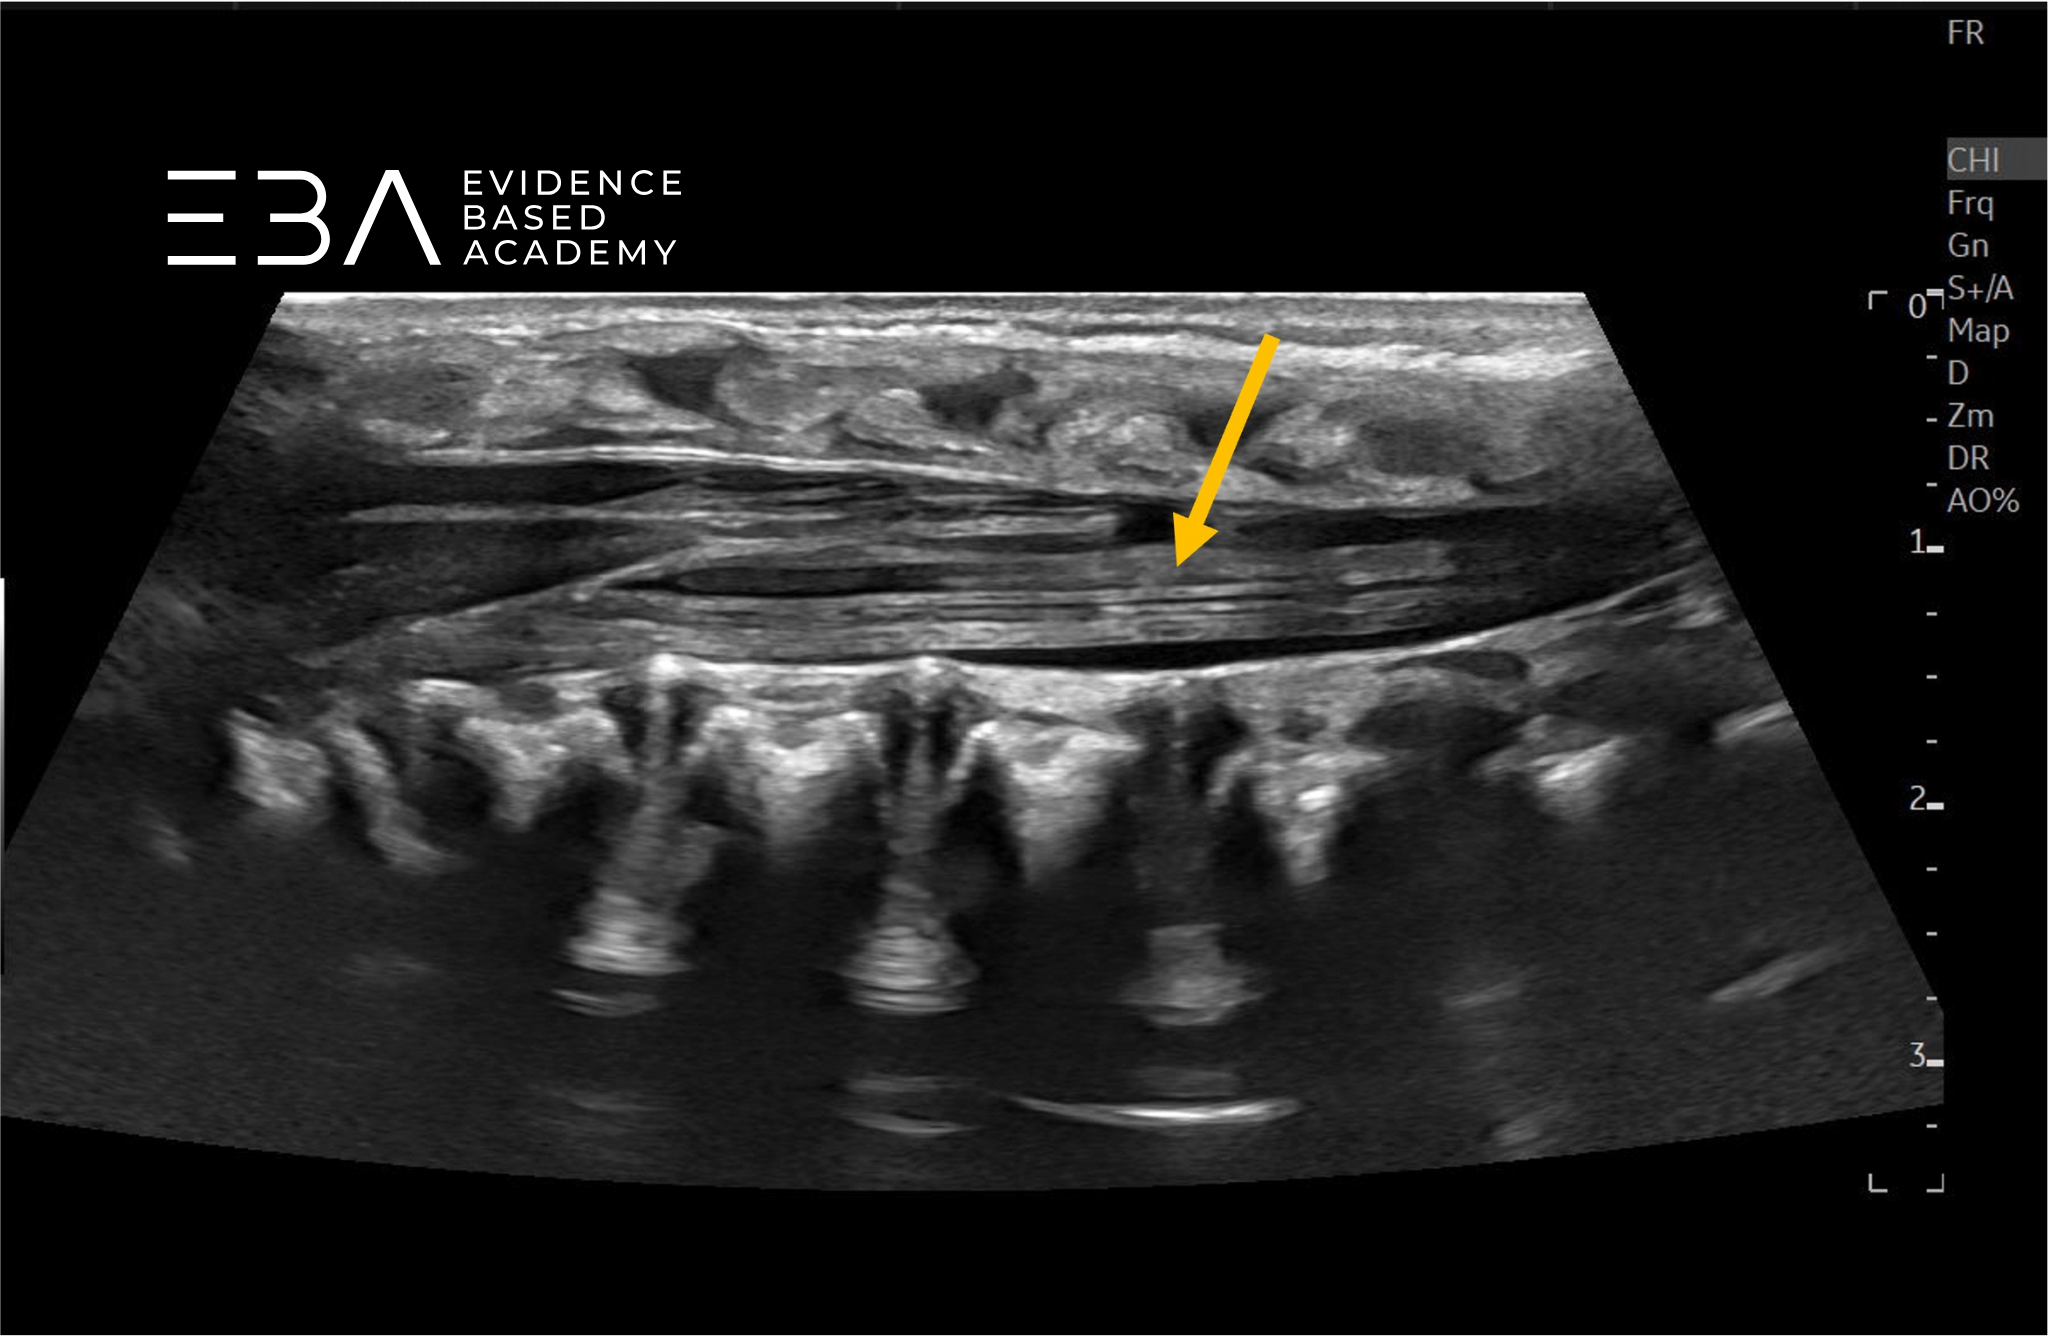

Obrazowanie dynamiczne

W trakcie USG kanału kręgowego należy przeprowadzić dynamiczną ocenę ruchomości rdzenia kręgowego i korzeni nerwowych. W niektórych przypadkach pomocne może być również USG w M-mode.

Należy pamiętać, że prawidłowy, nieuwięziony rdzeń również może nie wykazywać znaczącej pulsacji przez kilku pierwszych tygodni życia, co częściowo przypisuje się zmniejszonej objętości płynu mózgowo-rdzeniowego, wynikającej z fizjologicznego odwodnienia noworodków.

Przekrój podłużny przez kanału kręgowego – widoczna ruchomość ogona końskiego.